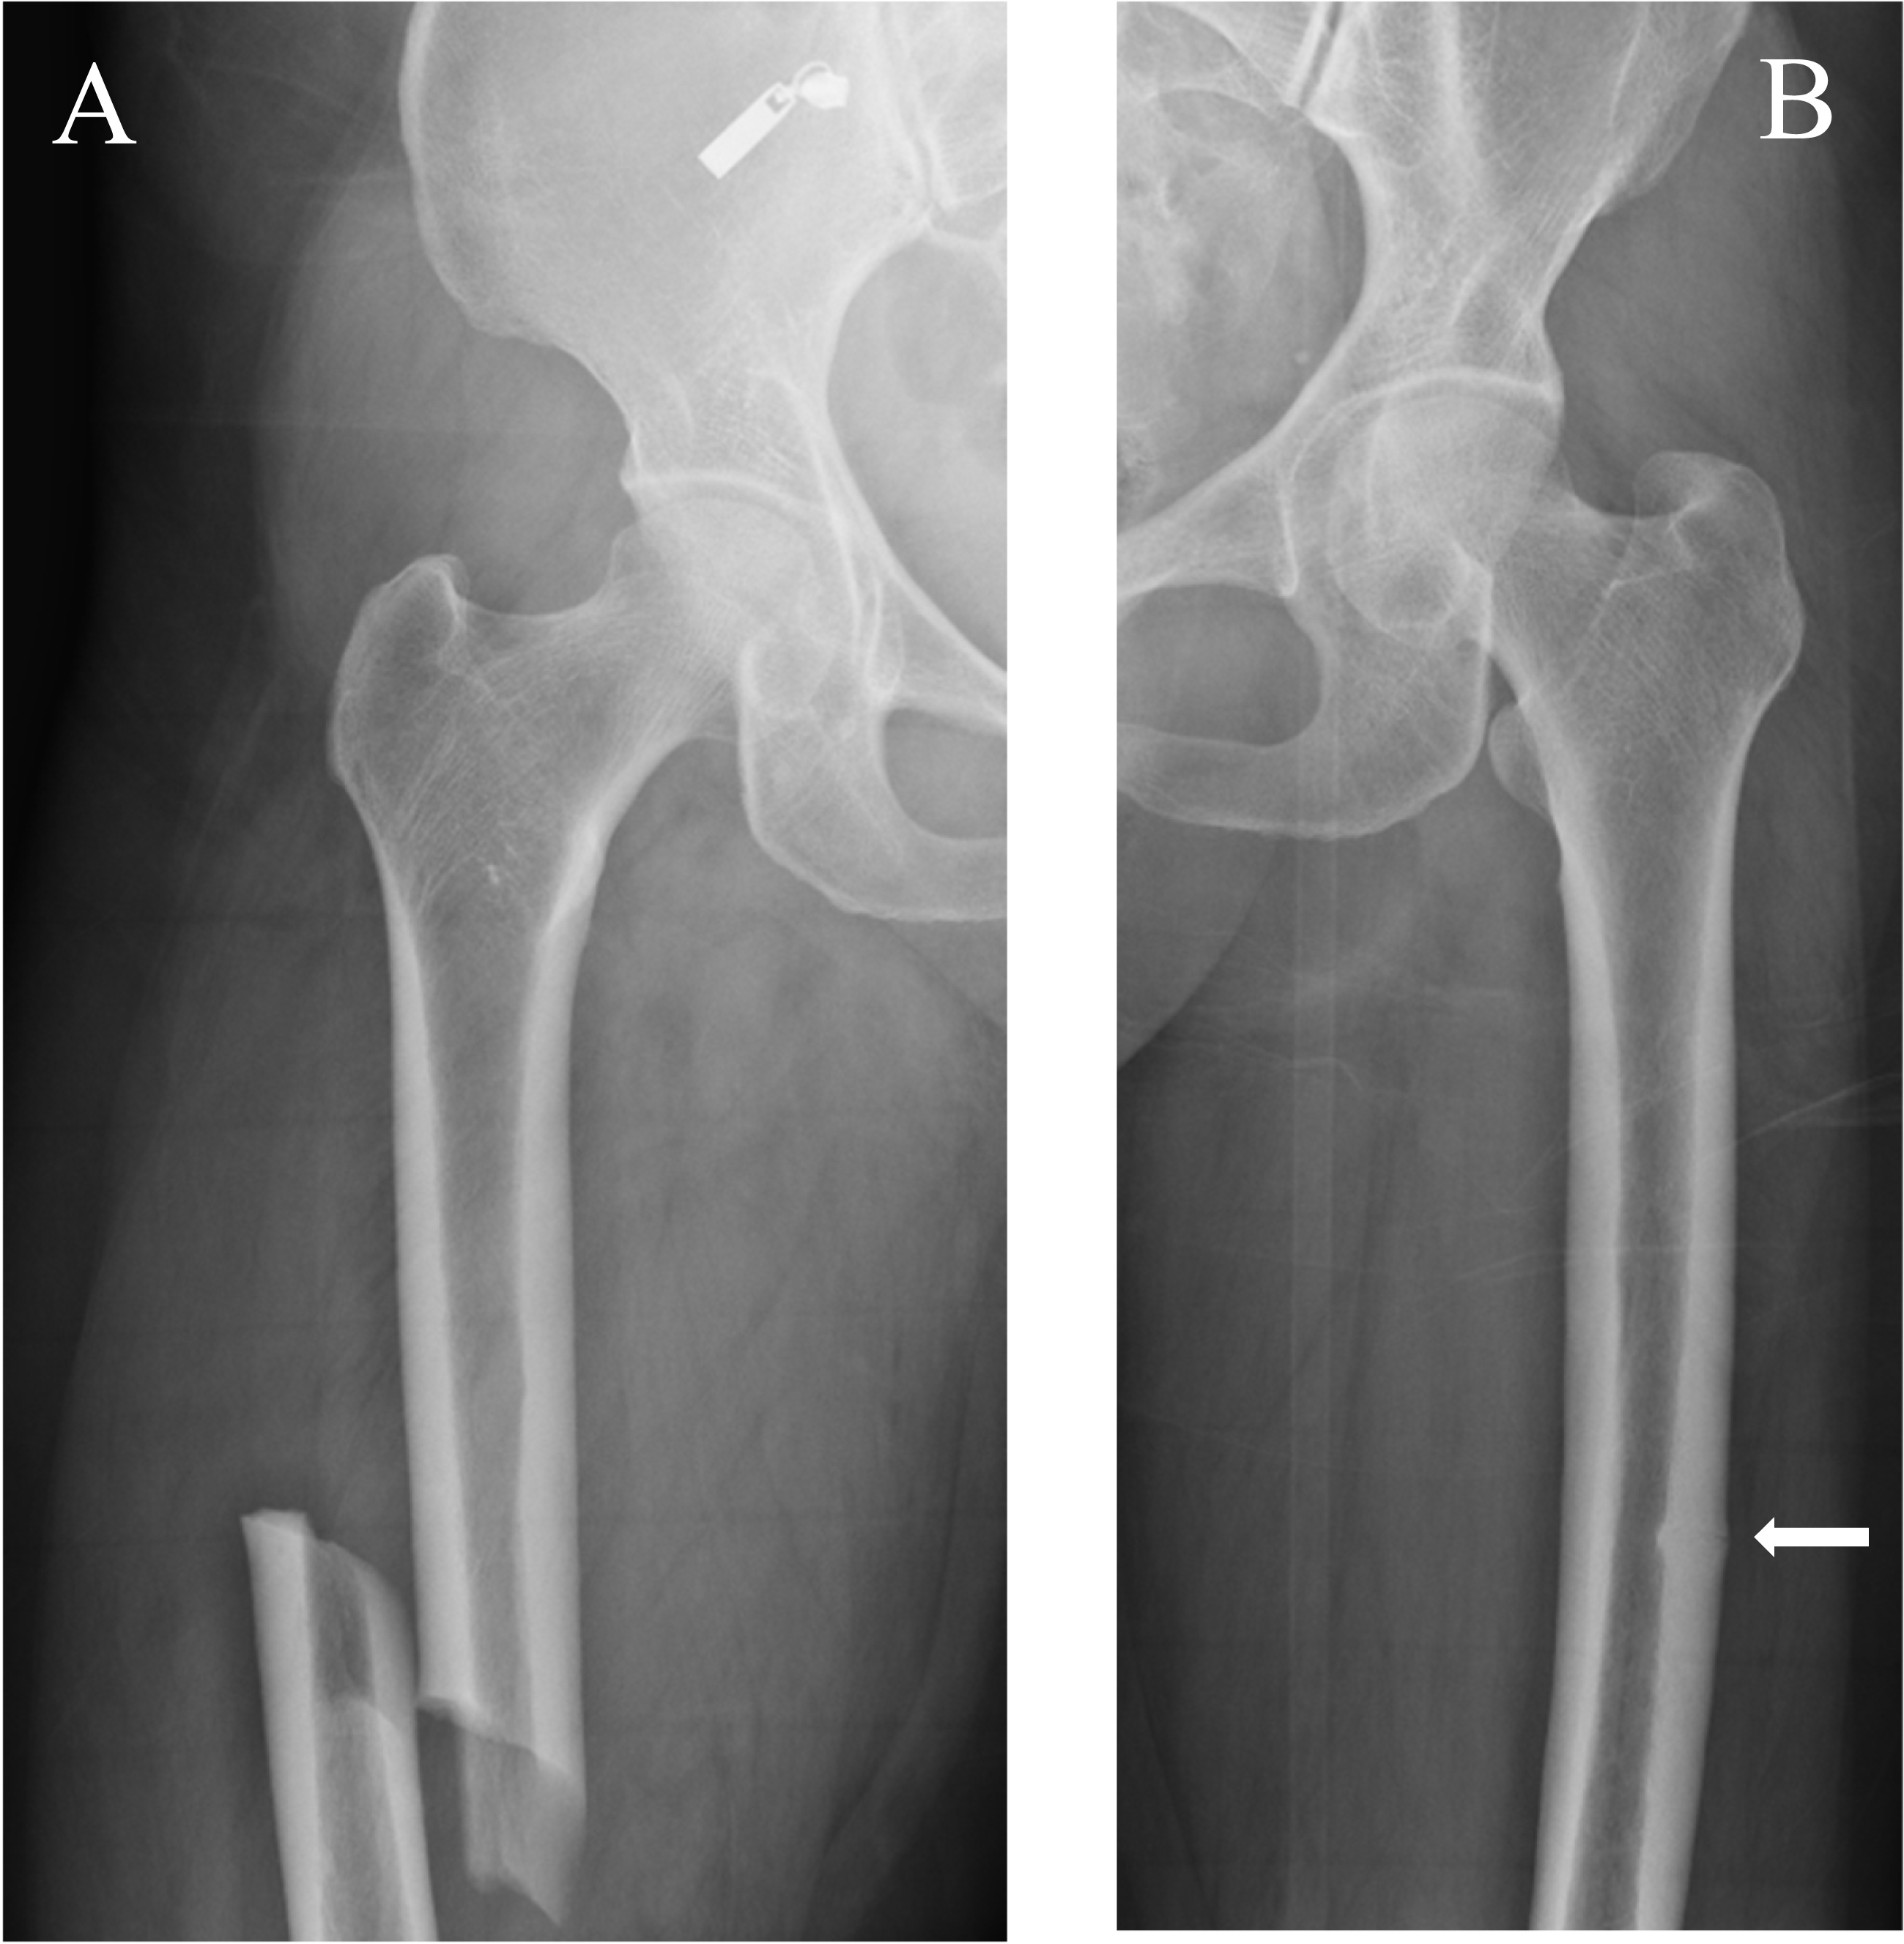

Genest F, Seefried L. ‘Subtrochanteric and diaphyseal femoral fractures in hypophosphatasia-not atypical at all’, Osteoporosis International, vol. 29, no. 8, pp. 1815–1825, 2018, https://doi.org/10.1007/s00198-018-4552-3

Charoenngam N, et al. Atypical femoral fracture in hypophosphatasia: A systematic review. Int J Endocrinol. 2023;5544148. https://doi.org/10.1155/2023/5544148.

Sutton RA, Mumm S, Coburn SP, Ericson KL, Whyte MP. Atypical femoral fractures during bisphosphonate exposure in adult hypophosphatasia. J Bone Min Res. 2012;27(5):987–94. https://doi.org/10.1002/jbmr.1565.

Coe JD, Murphy WA, Whyte MP. ‘Management of femoral fractures and pseudofractures in adult hypophosphatasia’, J Bone Joint Surg Am, vol. 68, no. 7, pp. 981–990, 1986, [Online]. Available: https://api.semanticscholar.org/CorpusID:46242610